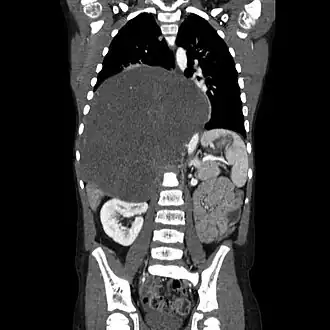

Diagnostic

Les ganglioneuromes peuvent être diagnostiqués par une tomodensitométrie, un IRM ou une échographie de la tête, de l'abdomen ou du bassin. Des analyses de sang et d'urine peuvent être effectuées pour déterminer si la tumeur sécrète des hormones ou d'autres produits chimiques en circulation. Une biopsie de la tumeur peut être nécessaire pour confirmer le diagnostic[3].